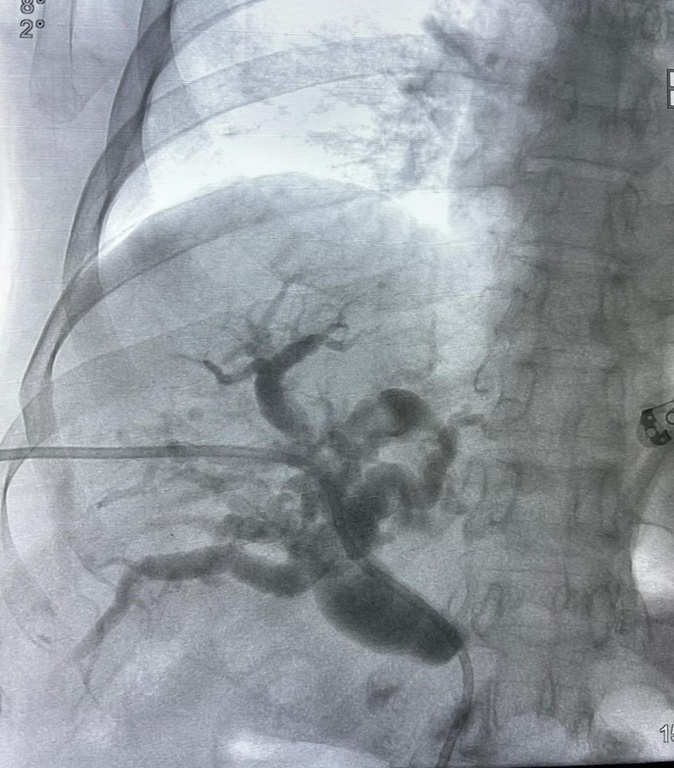

Imagem demonstra a anatomia biliar após o procedimento de cateterização, indicando a posição do cateter para drenagem biliar

No dia 26 de novembro, o Serviço de Radiologia Intervencionista do Hospital de Clínicas da Universidade Federal do Triângulo Mineiro (HC-UFTM), instituição vinculada à Empresa Brasileira de Serviços Hospitalares (Ebserh), realizou um procedimento bastante específico e minimamente invasivo de drenagem biliar. O diferencial dessa intervenção foi a execução da técnica percutânea (punção na pele) por hemodinâmica e ultrassonografia, com uso de cateter (pequeno tubo) fino e flexível.

Essa drenagem biliar corresponde a uma desobstrução das vias biliares, canais que transportam um líquido (a bile) produzido pelo fígado até o intestino e que é responsável por ajudar na digestão. “Este tipo de drenagem é comumente indicado para tratar obstruções causadas por tumores, cálculos biliares ou estreitamentos no canal biliar”, explicou o médico radiologista intervencionista Pedro Oliveira, que realizou este procedimento em um paciente de 72 anos, diagnosticado com tumor na cabeça do pâncreas que impedia esse fluxo natural da bile.

Conforme informou o médico, este procedimento realizado no HC-UFTM consistiu numa pequena incisão de agulha orientada por imagem (ultrassonografia e fluoroscopia) e nela um cateter fino e flexível foi inserido. Esse cateter permite os dois tipos de drenagem: a interna, com a desobstrução e restabelecimento do fluxo da bile; e a externa, caso o fluxo para o intestino não seja suficiente, com a coleta de parte da bile em uma bolsa externa. “É uma abordagem rápida, precisa e oferece o alívio imediato e a melhora significativa na qualidade de vida do paciente”, confirmou o especialista

Geisa Gomide, gastroenterologista do HC-UFTM e médica que está cuidando do paciente que foi submetido ao procedimento, contou que, como as vias biliares estavam obstruídas impedindo a passagem da bile, ela voltava e caía no sangue, levando a uma icterícia intensa (amarelamento da pele). “Isso se complica com prurido em todo o corpo, passando a se coçar continuamente, dia e noite.  Dois dias após o procedimento, esse paciente já estava menos ictérico e sem prurido”, explicou Geisa. Após a drenagem, o cateter, então, foi fixado na pele de forma segura para evitar deslocamentos e o paciente foi orientado com relação aos cuidados específicos com esse dispositivo.